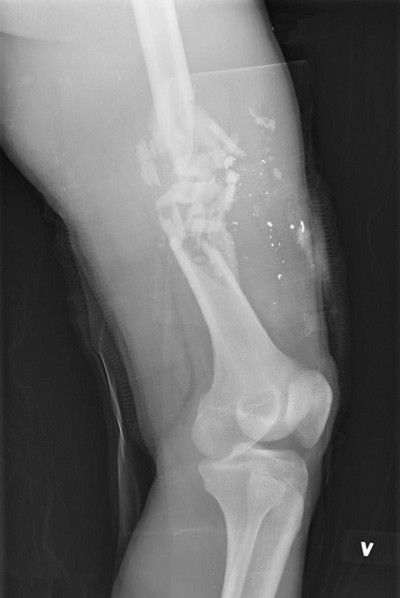

I Afghanistan eksponeres mange norske soldater for situasjoner som innebærer en betydelig risiko for å komme til skade. Dette gjelder spesielt trusselen fra tallrike veibomber (improvised explosive device; IED) (fig 1), og angrep fra motstandere som benytter rifler og rakettdrevne granater (rocket propelled granade; RPG) (fig 2 og 3).

Sju soldater kom alvorlig til skade. Mekanismene var skuddskade for fire av soldatene, mens de tre øvrige ble skadet av henholdsvis IED, splintskade fra mineeksplosjon og splintskade fra RPG. Noen av disse soldatene ble skadet i flere anatomiske regioner. Blant de sju soldatene var det to skader i ansikt, fem skader i truncus og tre skader i ekstremitetene. Median ISS-skår var 26 (spredning 5 – 35), median RTS-skår var 7,84 (spredning 5,15 – 7,84), og median beregnet sannsynlighet for overlevelse var 0,97 (spredning 0,71 – 0,99).

Ved 29 hendelser kom 28 soldater lettere til skade. Mekanismene var splinter eller rikosjetter fra skudd eller granatnedslag ved 22 hendelser, hvorav to var kombinert med brannskade, IED ved seks hendelser og ved en hendelse ble soldaten skadet av stein som ble kastet. Mange av soldatene ble skadet i flere anatomiske regioner, og skadene fordelte seg på følgende måte: hode ni, ansikt tre, hals en, brystkasse fire, abdomen en, rygg en, overekstremiteter 12 og underekstremiteter 12. Ingen hadde ISS-skår over 5, og ingen hadde redusert sannsynlighet for overlevelse.